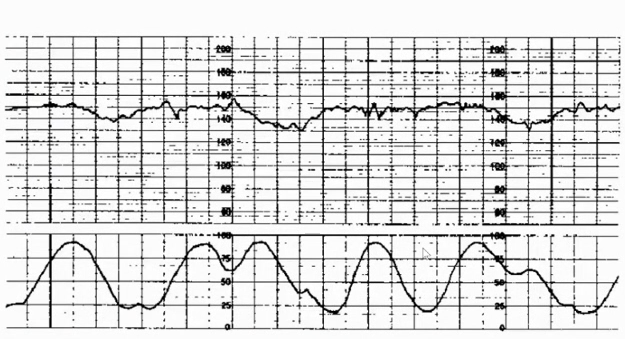

电子胎心监护是产科医护人员必备的一项基本功,只有掌握电子胎心监护的规范应用、识图技巧以及后续快速到位的应急处理,才能保证围产儿的健康安全。本期【每周一课】由四川大学华西第二医院的姚强教授就电子胎心监护的基本知识、判读要点及案例进行了详细的讲解。